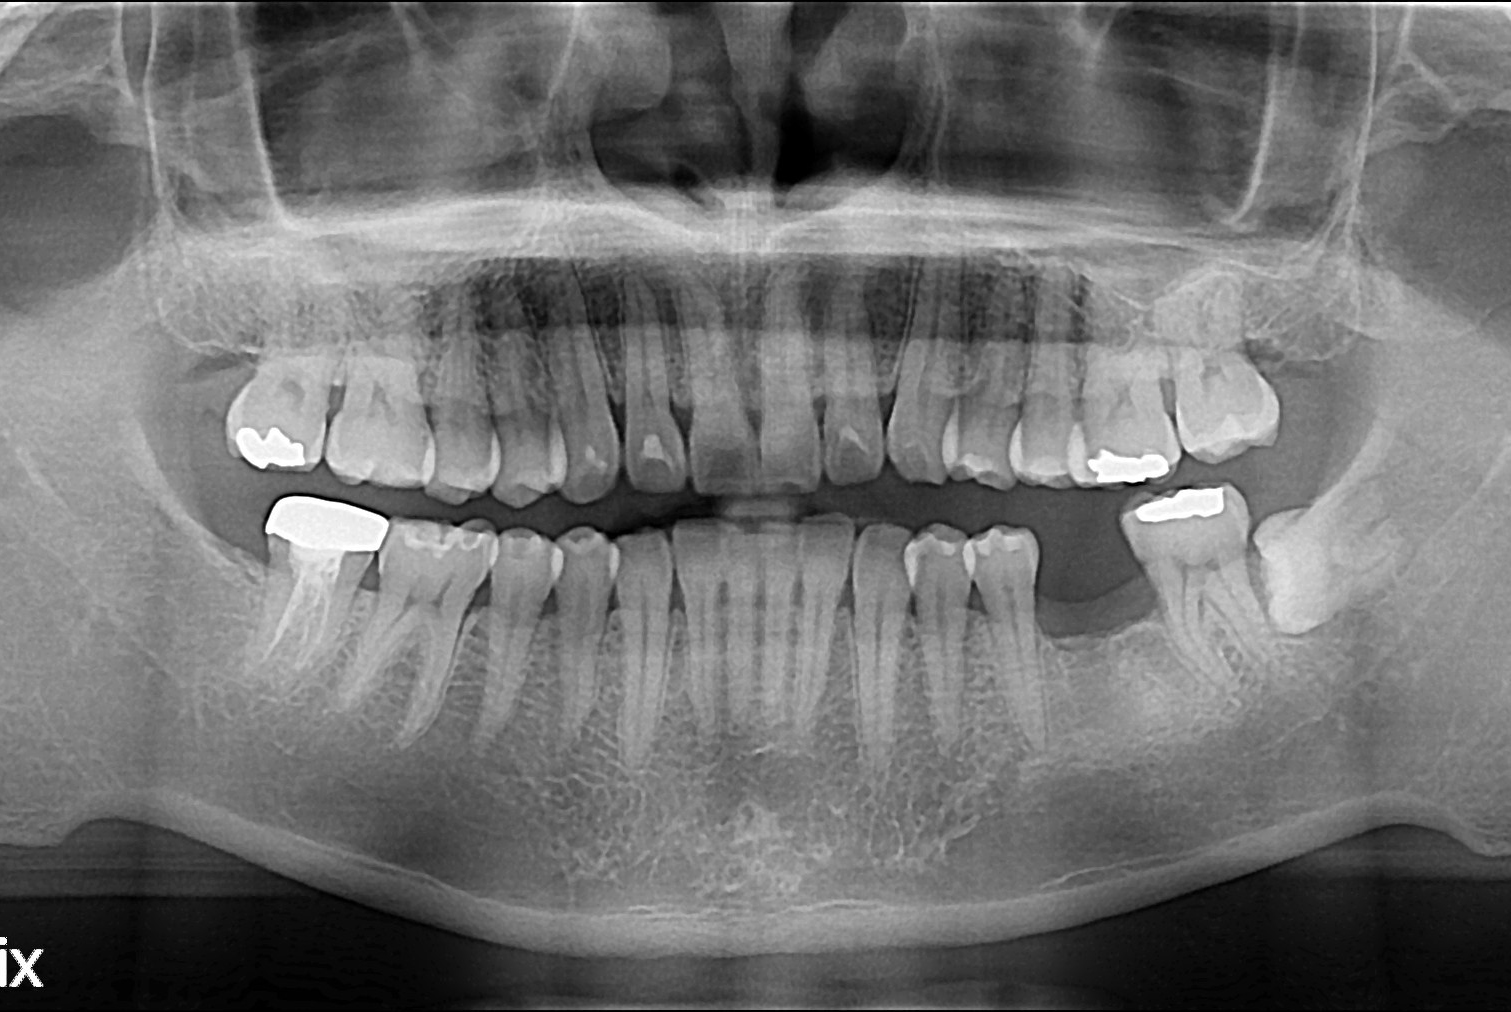

치료전 : 2016-01-21

치료후 : 2016-02-26

세종치과는 많은 환자와 다양한 케이스를 바탕으로 항상 편안한 임플란트 수술을 제공하고자 노력하고,

오래동안 튼튼히 쓸 수 있는 임플란트 수술을 가장 큰 목표로 삼고 있습니다